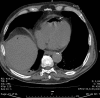

Fig. 5

Chest wall gangrene